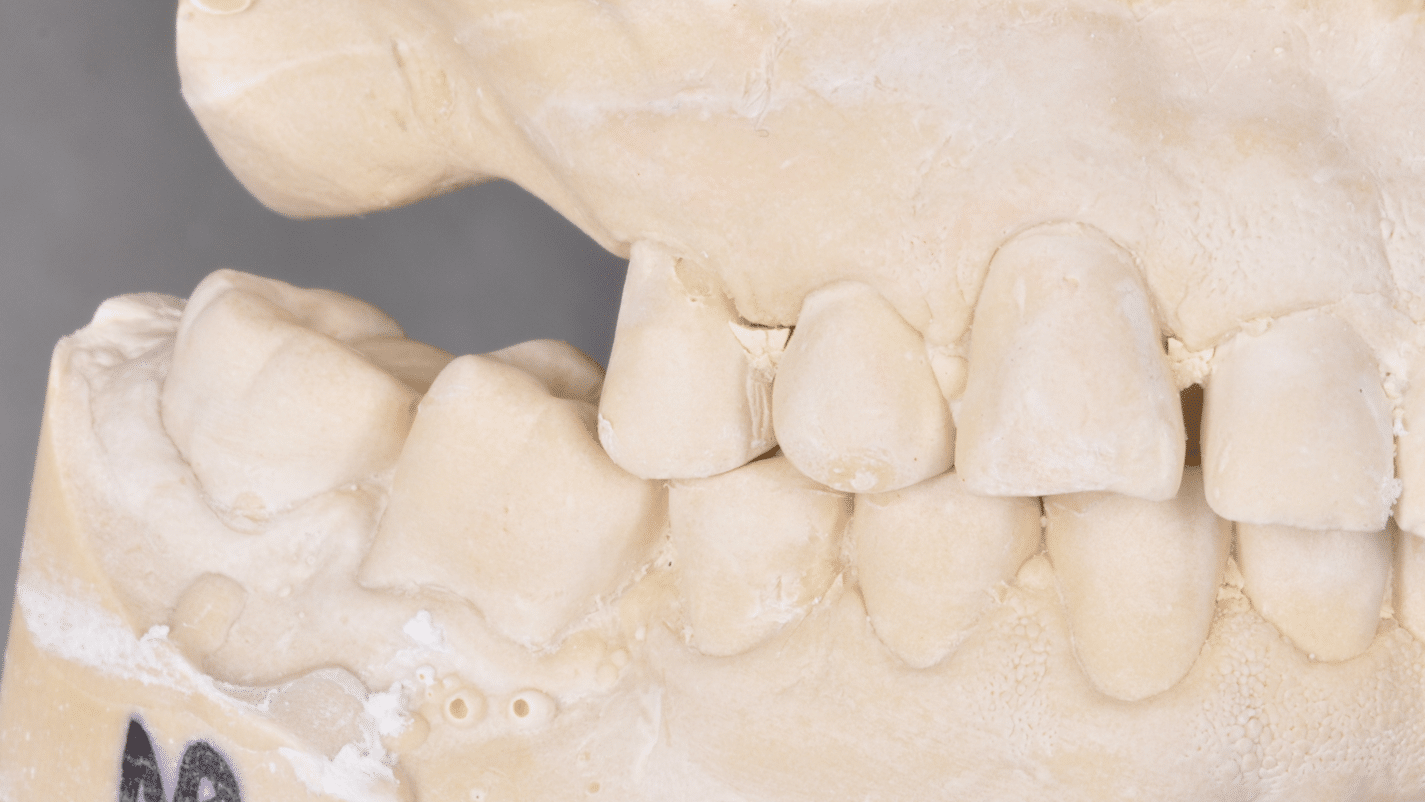

Împreună cu pacientul, am optat pentru inserarea implantelor cu ajutorul ghidului chirurgical pentru a plasa implantul în poziția protetică ideală și pentru a permite realizarea coroanelor insurubate pe implant. A fost efectuată scanarea digitală a arcadelor și a ocluziei pacientului, iar împreună cu tehnicianul radiolog de la DigiRay a fost suprapus fișierul .stl al amprentei digitale peste fișierul .dcm de la CBCT, utilizând software-ul 3Shape.

S-a planificat individual poziția și axul de inserție al fiecărui implant.

Doar astfel putem crea profilul de emergență corect al coroanei dentare, ceea ce permite conformarea papilei și a sulcusului.